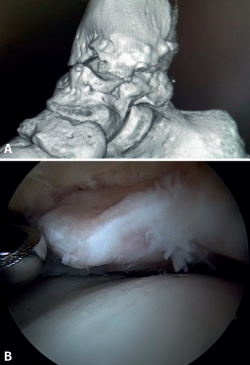

Anterior ankle impingement is defined as pain and/or limitation of range of motion that occurs with dorsiflexion of the ankle, due to the presence of soft tissue or bone interposed between the joint surfaces. A distinction is made between soft tissue impingement (synovial proliferation, thickening of Bassett's ligament, capsular adhesions), bony impingement (osteophytes or alterations in the ankle or hindfoot axis) (Figure 1) and mixed impingement (Table 1). AAI in turn can be subdivided into central, anterolateral and anteromedial impingement(8), with the first two being the most common presentations(9). Anterolateral AAI usually involves soft tissue, while anteromedial AAI is usually caused by a spatial conflict between osteophytes of the talar neck and anterior to the medial malleolus in dorsiflexion(9,10). AAI is the most common cause of anterior ankle pain that worsens with dorsiflexion. However, posterior impingement may be more frequent in certain patient groups, such as dancers or football players, due to repetitive movements in forced plantar flexion(4).

Figure 1. Bony impingement between the talus and tibia. A: ankle in plantar flexion; B: ankle in dorsiflexion showing impingement between the two osteophytes.